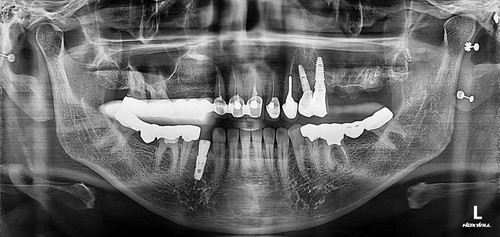

저희 치과에 오신 거는 발치한 날로부터 약 3주가 지난 상태로 오셨는데 발치한 치과에서는 한달이 안 되었기 때문에 더 기다려 볼 것을 권유 받으셨었습니다. 그런데 환자분이 제가 구강상악동누공에 대하여 작성한 포스팅을 보시고 저희 치과를 방문하시게 되었습니다. 보통 발치한지 3주가 되면 구강상악동천공의 단계를 지나서 구강상악동누공의 상태로 발전하게 됩니다. 내원 당시에 찍은 시티에서 10mm 이상의 천공이 확인 되었고 막아 놓았던 비흡수성 차례막을 제거하니 자연 치유될 정도의 천공이 아닌 걸로 확인하고 상악동누공폐쇄술을 시행하기로 하였습니다.

보통 5mm보다 작은 천공은 상악동염증이 없는 경우에는 자연치유 된다고 주장하는 논문도 있고 3mm 보다 작은 천공은 자연치유 된다고 말하는 논문도 있습니다. 하지만 제가 현재까지 약 30명 가량의 상악동누공폐쇄술을 했는데 환자 중에서 4mm 정도의 천공이 자연치유되지 않아서 폐쇄술을 한 경우도 2명 정도 있었습니다. 이걸로 보아서 5mm 보다는 3mm 보다 작은 천공이 자연치유 된다는 주장이 더 합당하다고 생각됩니다. 그래서 이 환자분은 10mm 이상의 매우 커다란 천공이 있었기 때문에 반드시 폐쇄술을 시행해 주어야 하지만 잇몸 상태가 너무 안 좋아서 잇몸이 어느 정도 치유될 때까지 기다린 후에 상악동누공폐쇄술을 계획하였고 성공적으로 잘 막혔습니다.

상악동누공폐쇄술이 성공하면 그 다음 단계로는 치조골 이식과 임플란트 식립을 해야 하는데 간혹가다 일반적인 상악동거상술에 비하면 누공이 있었던 부위는 상악동점막과 잇몸살이 유착되어서 힘든 경우가 많습니다. 물론 폐쇄술을 시행하면서 상악동에 뼈이식을 동시에 하는 것도 하나의 방법이 될수 있겠으나 성공했을 때 뿐만 아니라 누공폐쇄술이 실패했을 때를 가정한다면 통상적으로 동시 뼈이식을 시행하기에는 다소 위험성이 따르는 것이 사실입니다. 그래서 이 환자분은 안전하게 단계적으로 진행하기로 하였으며 누공폐쇄술이 성공한 후에 상악동 측방거상술을 시행하였고 이식한 뼈가 충분히 굳은 후에 임플란트를 식립하였습니다.